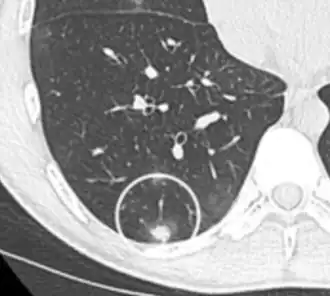

- Margin morphology: a spiculated margin is a risk factor for cancer.[8] Benign causes tend to have a well defined border, whereas lobulated lesions or those with an irregular margin extending into the neighbouring tissue tend to be malignant.[10] In particular, spiculations are highly predictive of malignancy with a positive predictive value up to 90%.[9] Also, a "notch sign", which is an abrupt indentation of the nodule, increases the risk of cancer, but may also be found in granulomatous diseases.[9]

-

subpleural nodule.[9] -

Round well-delineated solid lung nodule with smooth border.[9] -

Lobulated nodule.[9] -

Spiculated lung nodule.[9] -

A "notch sign".[9] -

A triangular perifissural node can be diagnosed as a benign lymph node.[9]